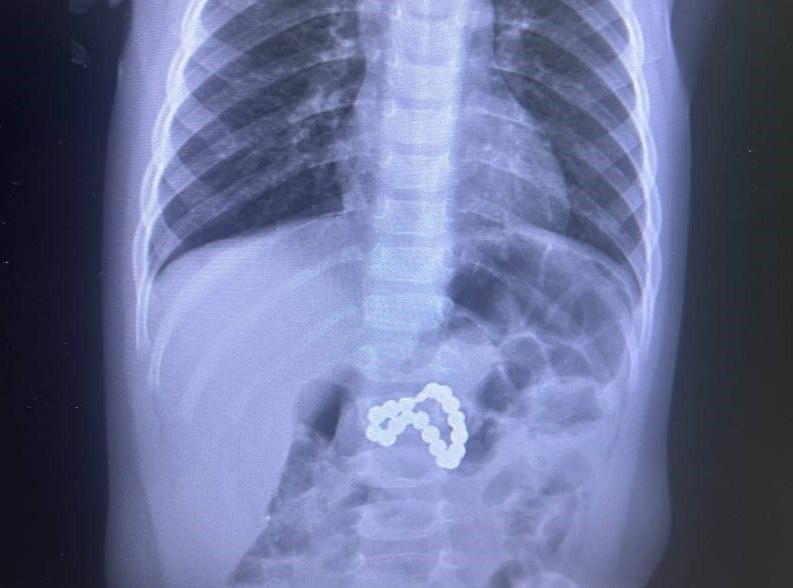

Сургутские врачи спасли проглотившую магниты девочку

Ребенок чуть не лишился желудка.

В Центре охраны материнства и детства в Сургуте смогли спасти ребенка, который серьезно пострадал от проглоченных переносных магнитов. Девочку в крайне тяжелом состоянии экстренно доставили в больницу, сообщает телеканал «Мегаполис».

«Предметы фактически разорвали желудок и кишечник. Медикам пришлось в срочном порядке делать эндоскопию, сшивать внутренние органы и переливать кровь», — рассказало подробности издание. Спасением девочки сутки занималась бригада хирургов, реаниматологов, эндоскопистов и медицинских сестер.

Фото: Сургутский центр охраны материнства и детства